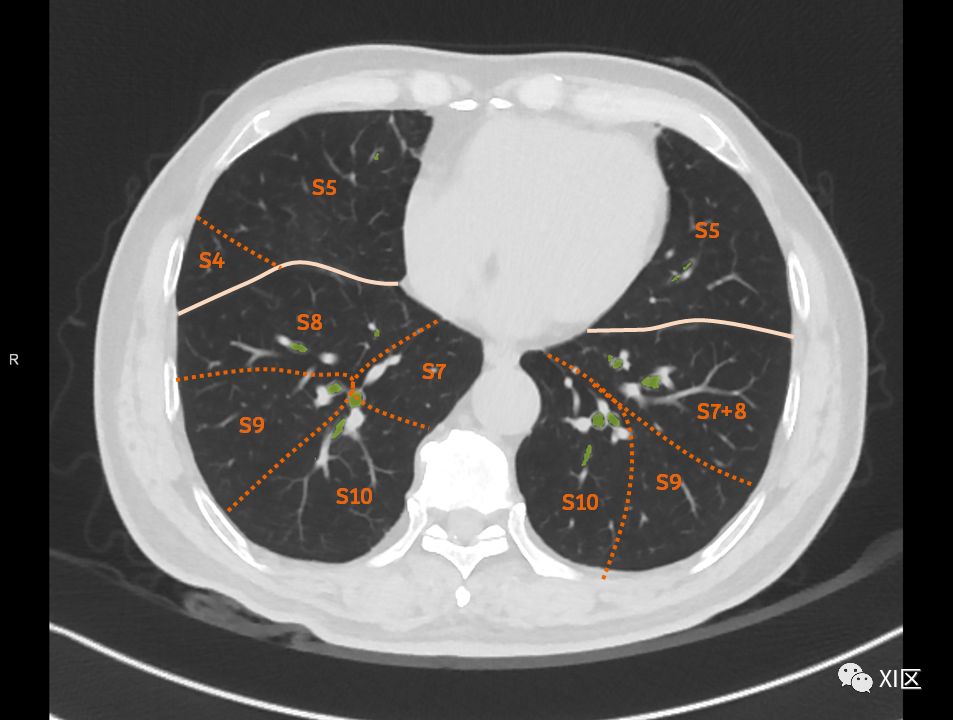

肺的断层分段示意图 医学百科网 | YxBaike.Com

在进行肺的分段时,可以上下观察浏览,沿着相应气管的走形可以更容易准确地进行分段。